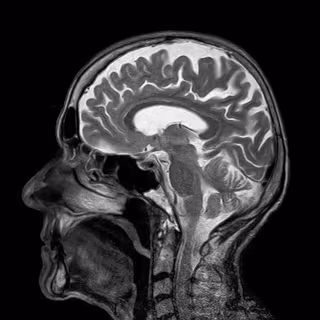

Crean un nuevo método no invasivo de monitorización de la presión intracraneal

CEREBRO

PIXABAY